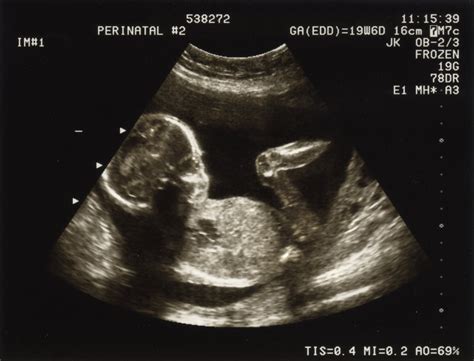

Testul folosit pentru a verifica decesul fetal în al doilea trimestru este o examinare cu ultrasunete pentru a vedea cum se dezvoltă copilul. Analizele recomandate după o sarcină oprită din evoluție includ ecografia și probele de sânge. Valorile beta HCG în sarcina oprită din evoluție scad progresiv.